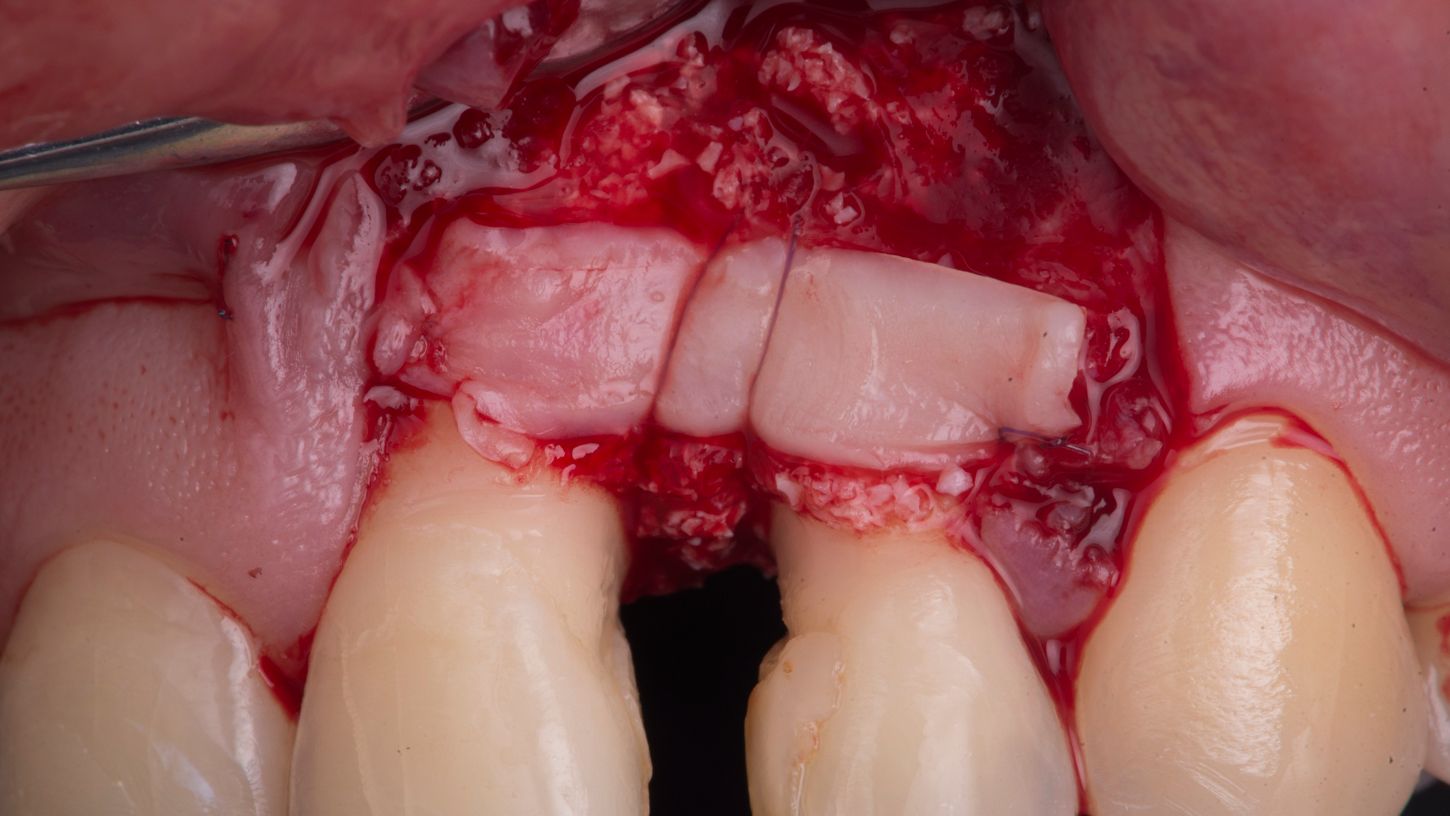

The periodontal defect was filled with Straumann® XenoGraft (Fig. 8) and covered with a second layer of Straumann® Emdogain® (Fig. 9).

A CTG was harvested from the palate and stabilized over the bone graft with a horizontal mattress suture (Fig. 10).

Fig. 10